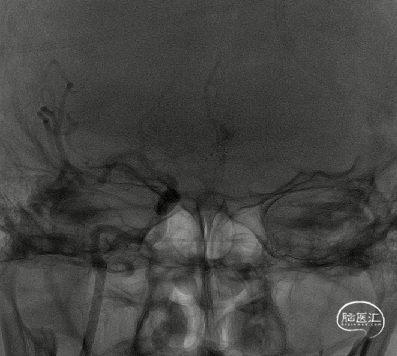

术前造影

右侧颈内动脉闭塞,同时颈外动脉有血栓,闭塞。

右侧颈内动脉起始部呈现“火焰征”,提示假性闭塞,远端眼动脉未见代偿。

前交通开放,左侧A1供应双侧A2。

后交通动脉开放,右侧大脑中动脉可见部分显影。

提示病变为栓塞性串联病变,增加手术难度。这样我们就考虑首先争取单纯抽吸快速开通颈内动脉,然后再SWIM技术取通大脑中动脉。